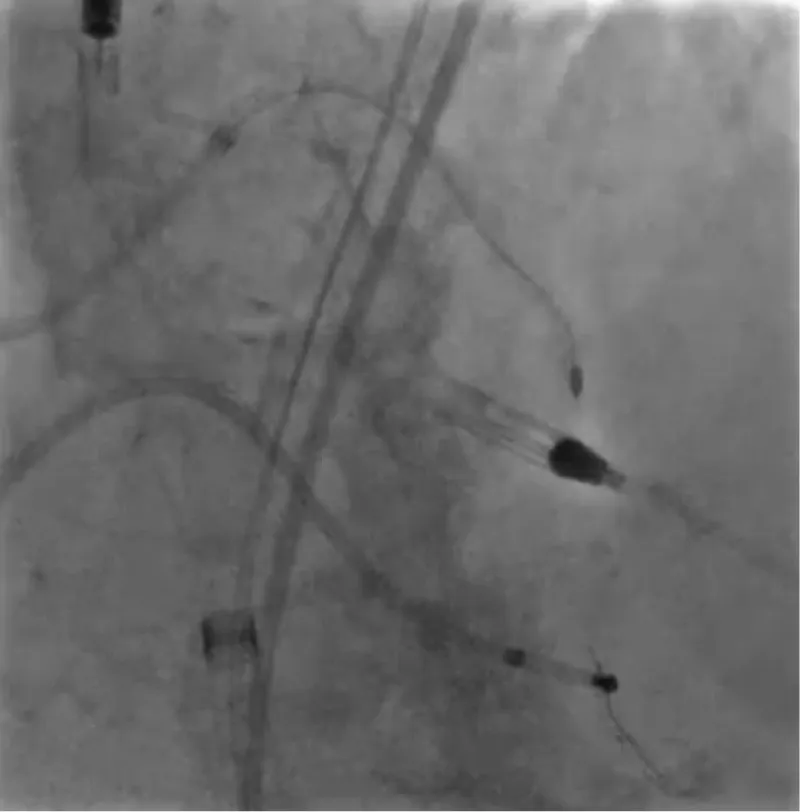

With the support of deep sedation, an angio-guided right femoral access was obtained, and a 12F introducer was advanced. We crossed the aortic valve with an Amplatzer left 1 catheter with a 0.035” wire and exchanged the wire with an extra-stiff Safari. We performed aortic Valvuloplasty with a Nucleus balloon 18 x 40 mm. (Figure 7) Then, we exchanged the wire and advanced an IMPELLA CP device, starting a protected PCI on LM. (Figure 8) An EBU 4.0 catheter was advanced, the stenosis was crossed on the Left Main (LM) and mid-Left Anterior Descending artery (LAD) using a BMW guide wire, and with the aid of a microcatheter a 0.014” Rotawire was positioned, followed by rotational atherectomy using a 1.5 mm burr on LM and mid LAD, (Figure 9) and a 2.0 mm burr on LM alone (Figure 10). This was followed by predilation with a 2.5 x 20 mm SC balloon and the implantation of a 2.5 x 32 mm Synergy drug-eluting stent (Figure 11). Then, the Left Main was predilated with a 3.5 x 12 mm NC balloon, and a 4.0 x 15 mm Xience Sierra drug-eluting stent was implanted and post-dilated with a 4.5 x 8 mm SC balloon (Figure 12). Immediate angiographic control confirmed a successful result. Then we removed the IMPELLA CP device and advanced a 14F e-sheath Edwards on the right femoral artery, crossed the aortic valve with a Safari extra-stiff wire, and performed a Sapien 3 23 mm valve implantation with a good angiographic result (Figure 13). Post-procedural echocardiographic and angiographic assessment confirmed the valve was correctly positioned, with no significant gradient and a minimal residual leak. The procedure was uneventful, and the patient was discharged on the fourth day with triple therapy: Aspirin 100 mg once daily, Clopidogrel 75 mg once daily, and Apixaban 2.5 mg twice daily. At the quarterly follow-up, the patient reported hospitalization for anemia, requiring a transfusion of 3 units of packed red blood cells. Endoscopic exams were negative, and hypochromic, normocytic anemia persisted. Given the patient’s CHA2D2-VASc score of 5, HAS-BLED score of 4, and recent dual Drug-Eluting Stent (DES) implantation, she was admitted for left atrial appendage percutaneous closure. Before this procedure, a repeat coronary angiography showed good results in the previously implanted stents (Figure 14). Subsequently, through a right femoral percutaneous approach using a 12F introducer, a 22 mm Amulet device was positioned for left atrial appendage closure (Figure 15). The procedure was completed without complications. At the 4-year follow-up, the patient presented in good hemodynamic status, with an echocardiographic ejection fraction of 55%. She continued on clopidogrel 75 mg once daily therapy.

Figure 11: PTCA on LAD.

Download Image